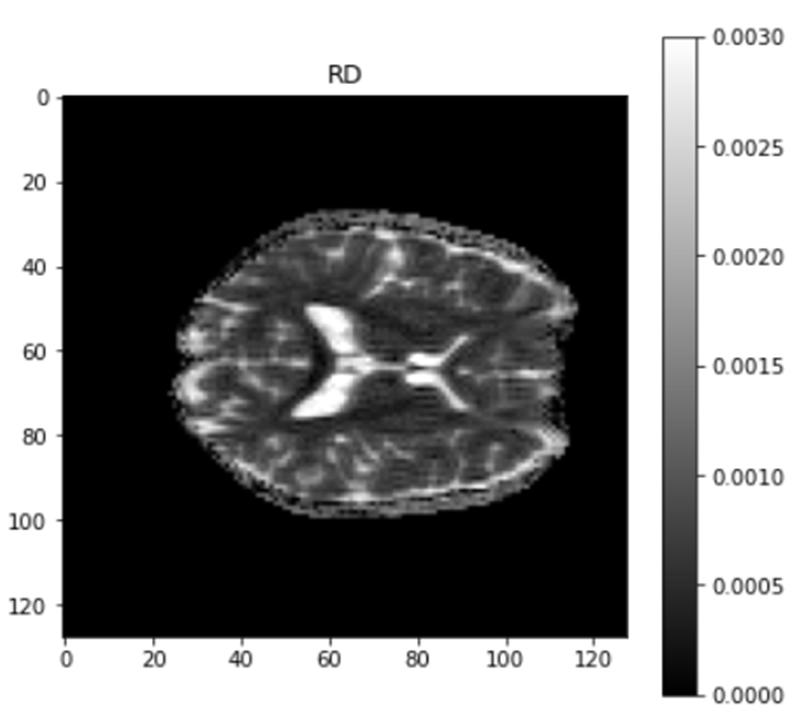

Axial diffusivity (AD) and radial diffusivity (RD) are the Additional measures necessary to further define the tensor if two tensors with different forms provide identical FA values. AD describes the diffusion rate along the primary axis of diffusion, along ( ), or parallel to the axon (and hence, some works refer to it as parallel diffusivity). On the other hand, RD is the average diffusivity along the minor axes(being named perpendicular diffusivity). Where both are measured in mm^2/s.

When it comes to AD and RD maps, we are able to identify changes in the axonal parameter by adjusting the white matter area. This allows us to better understand the connections between neurons. In AD, the main water movement is strongly focused, along primary axis. but in RD, it is focused transverse to the long axis.

Fig. 11 Output RD map